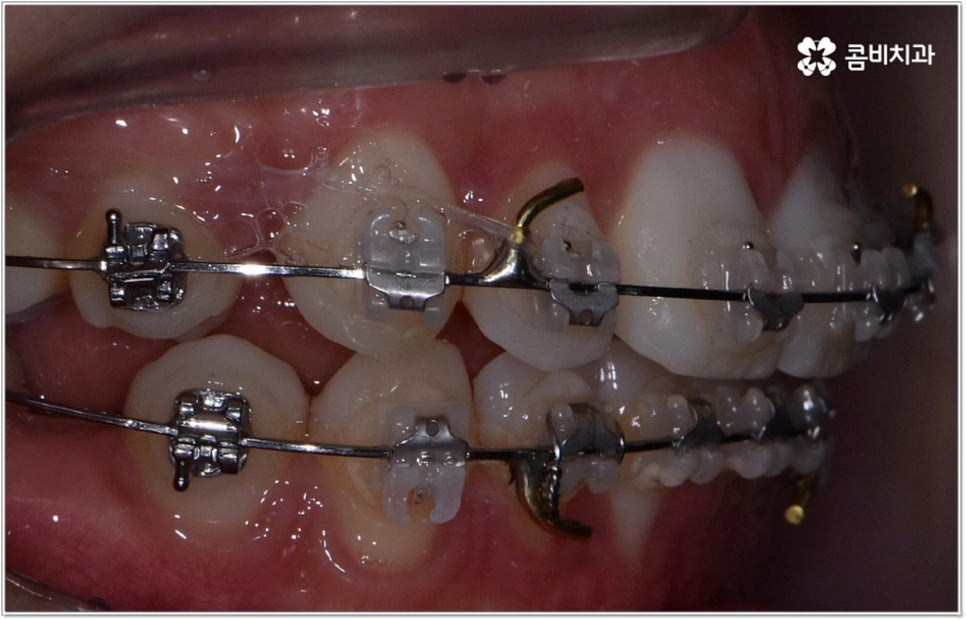

청소년기는 교우 관계에 영향을 많이 받고 외모에 민감할 때라 교정기에 대한 반감이 있을 수 있으나 바로 이때가 치아 이동에 있어 매우 중요한 시기이므로 제대로 이해할 수 있도록 차근차근 설명해 줄 필요가 있는데요. 12~15세 사이, 즉 초등학교 고학년에서 중학교 저학년 사이가 유치에서 영구치로 거의 다 교체되고 잇몸뼈가 계속해서 성장하는 나이이기 때문에 상악과 하악의 균형잡힌 발달을 유도하면서 부정교합을 바로잡고 치열을 가지런하게 만드는데 보다 빠르고 효율적인 만큼 가능하다면 이 시기를 놓치지 않는게 중요한 거예요. 물론 성인분들도 상황에 맞게 교정 치료를 진행할 수 있지만 부정교합의 종류와 정도에 따라 성장기 교정 치료를 진행하는 것이 좀 더 나은 케이스가 있으니 아이의 치열에 관심을 가지고 정확하게 알아보시는 것이 도움이 될 수 있습니다.

무리하지 않고 돌출입치아교정 과정을 진행하기 위해서는 먼저 꼼꼼한 검진 및 분석에 따른 철저한 맞춤 치료 계획 수립이 중요하다고 할 수 있는데요. 특히 3D CT 및 모르페우스 시스템을 통해 현재 아이의 치열이나 연조직, 상하악 관계 등을 자세히 살펴보고 안모 분석 후 교정 치료가 끝난 예상 모습을 시뮬레이션해서 보여주면 환아의 흥미를 유발하고 앞으로 진행될 사항에 대한 이해도를 높여줄 수 있어 긍정적인 영향을 줄 수 있으니 정밀 검진 장비를 갖추고 숙련된 의료진이 치료하는 치과에서 돌출입치아교정 과정을 진행하시길 권유드리고 있어요.

성장기 교정의 경우 턱성장 추이에 맞추어 섬세하게 치아 이동 속도를 결정해야 하므로 구강 검진 외에도 성장판 검진 등을 통해 아이의 전반적인 발달 상황에 대한 유기적인 이해를 바탕으로 치료를 하는 경험 많은 담당의 선생님께 시술을 맡기실 필요가 있습니다. 또한 이렇게 뛰어난 노하우와 기술력을 갖춘 것 뿐 아니라 사전 상담, 전 교정 과정 그리고 사후 관리에 이르기까지 지속적인 소통을 통해 불편한 점이 없는지 세심하게 살피고 개개인의 상황 및 구강 건강을 전체적으로 신경써서 케어해 주는 의료진과 함께 한다면 환아 뿐 아니라 부모님의 입장에서도 더욱 안심이 되고 좋을 거예요.

돌출입치아교정 치료에 있어서 방법이나 기간 등 자세한 사항은 환자분들에 따라 달라지는데 다른 문제 없이 치아의 각도만 앞으로 뻐드러진 경우에는 비교적 빠르고 간편하게 개선이 가능한 반면 부정교합 정도가 많이 심각하거나 골격적인 원인이 굳어진 경우 외과적 악교정수술이 병행 돼야 할 수도 있는 만큼 말씀드린 것처럼 제때 검진부터 꼼꼼하게 받아보시길 권유드리고 있습니다.